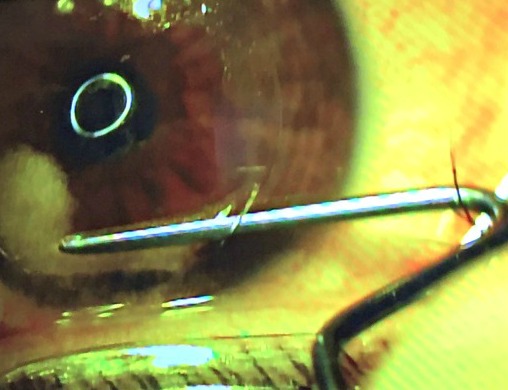

Meanwhile, my mother/chauffeur/caretaker/photographer took pictures of the whole thing while I was having the procedure. While I’ll admit it took me a few days to really look at these, it does show almost every part of the procedure – one shot at a time.

So here’s your disclaimer: if you want to see some really, up close photos of my procedure, be my guest. If your stomach is a little weak, I wouldn’t do it. Just remember, these photos are in no order of the procedure, but they are pretty wild what happens in the Lasik Suite. However, if you want to see a video that explains exactly what happens in a procedure like this, then take a look at this.